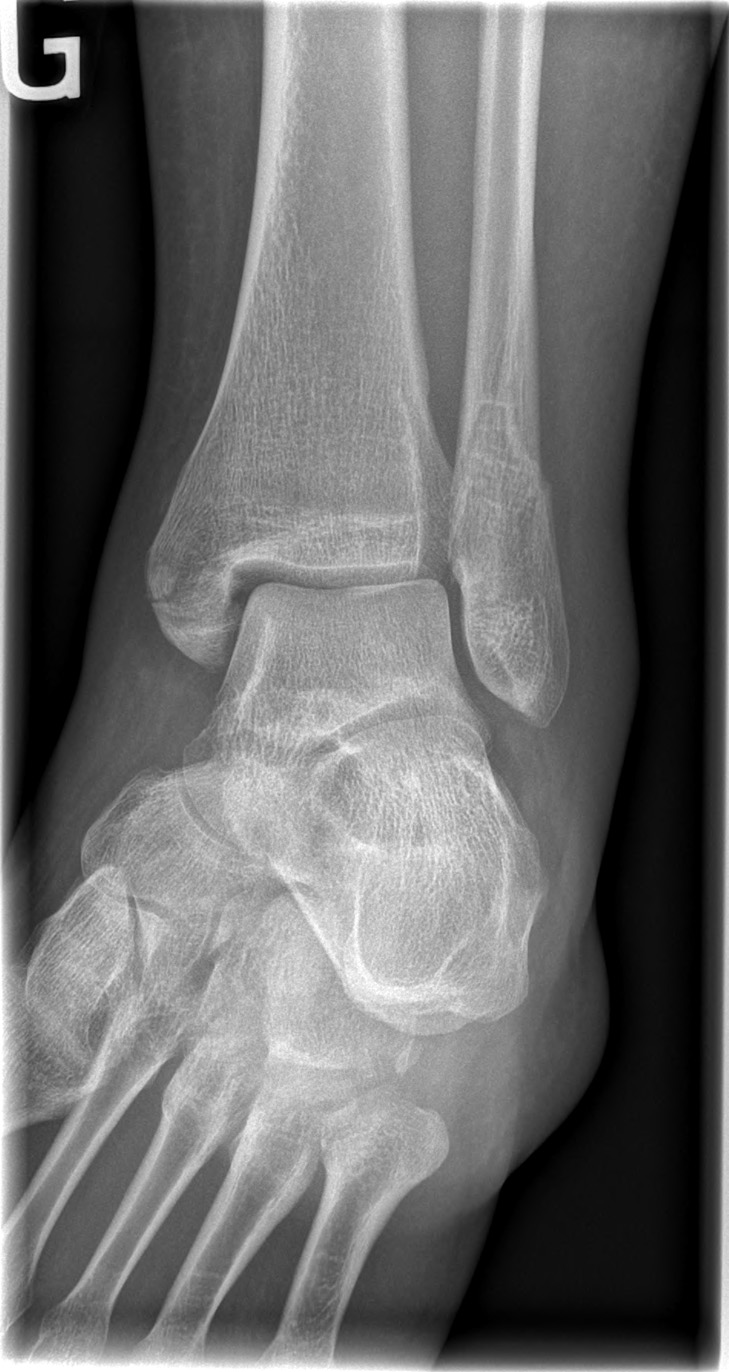

26-year-old male:

Ankle eversion trauma while playing soccer.

Bimalleolar fracture

Lateral malleolus oblique fracture (Weber B) concomitant to a medial malleolus transverse fracture.

Intact posterior malleolus

The posterior malleolus appears intact.

Anteroposterior

• Anteroposterior